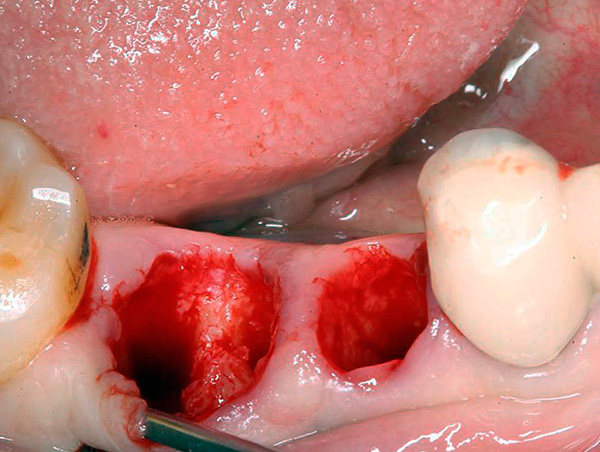

Nella foto in basso: nuovi fori dopo aver rimosso due denti contemporaneamente:

Pertanto, una temperatura elevata di 1-2 giorni dopo la rimozione non dovrebbe essere considerata come una patologia, ma dovrebbe essere monitorata 2 volte al giorno alla stessa ora (ad esempio, al mattino presto alle 8 e poi a tarda sera alle 20:00). Se la temperatura è superiore a 38,5 ° C o dura più di 2 giorni, con letture mattutine elevate, questa è l'occasione per consultare un medico.